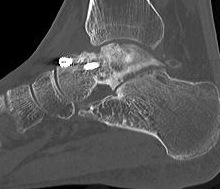

CT

Talus ACN CT 1Talus AVN CT 2